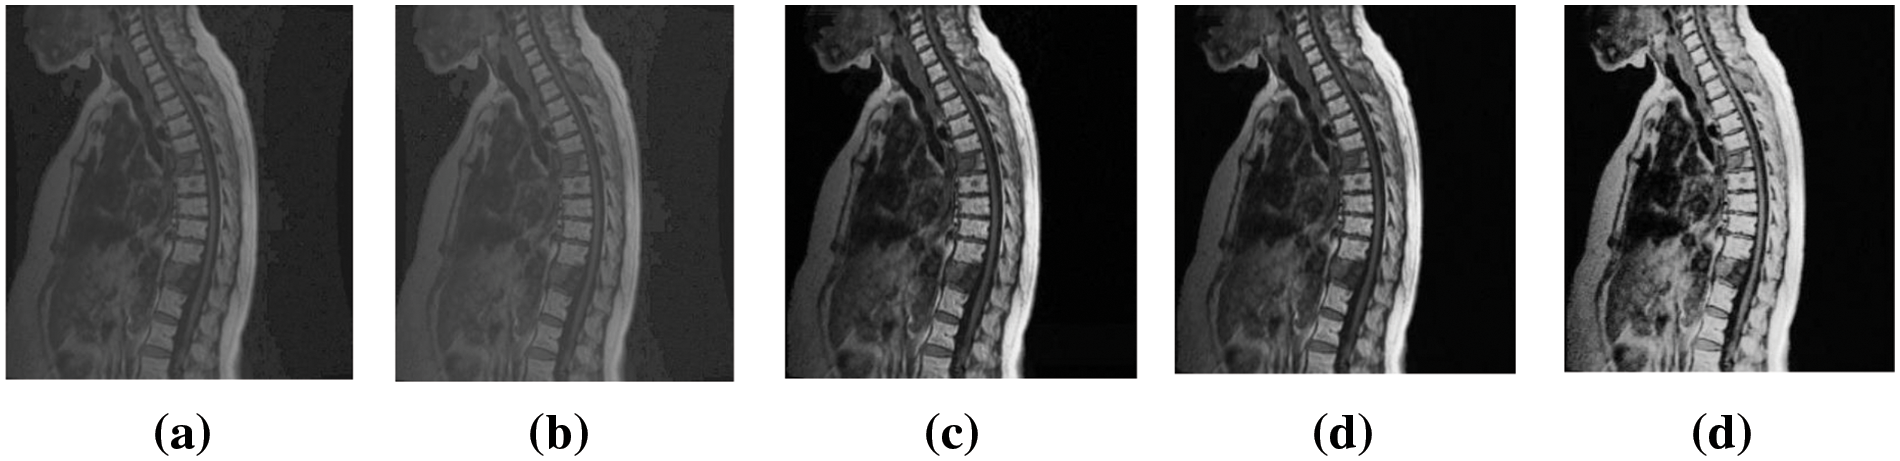

Fig. 6 of this study contains a representation of these six medical images, the selection of the medical images is limited to the experiment of this paper considering limitation in space, with all experimental analysis of marked image of 2 bit per pixel (bpp), which is the highest rate of embedding in this paper.

Figure 6: Medical images from NBIA and Medpix

Fig. 12 is a visual evaluation of marked images of Chest03 at an embedding rate of 2 bpp of ACERDH, RHCRDH, RDHACEM, ACERDHBS with the proposed method, indicating its performance metrics in Table 4.

Figure 12: Marked images of “Chest03” using the ACERDH, RHCRDH, RDHACEM, ACERDHBS and proposed algorithms at 2 bpp

The MOS results presented in Table 4 represent the evaluations provided by healthcare professionals when assessing the prognosis of the case utilizing each improved image. The results demonstrate that the proposed method consistently produced higher-quality images compared to the existing method for all test images. This suggests that the enhanced images generated by the proposed method are more suitable for diagnosis and treatment, among other methods.